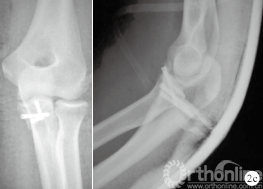

图 2 患者,男,23 岁,左侧尺骨冠状突骨折(Ⅱ型)

c.术后2天肘关节正侧位 X 线片